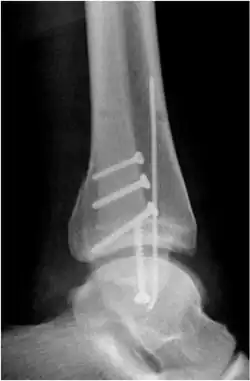

Osteosynthese der Fibula

Bei allen anderen Brüchen mit verschobenen Knochenbruchstücken und bei Verletzung der Gabelbänder ist in der Regel eine offene Operation mit Knochenverschraubung (Osteosynthese) und Bandstabilisierung notwendig. Die einfachste und biomechanisch stabilste Versorgung erfolgt mit mindestens zwei bis drei Zugschrauben je nach Länge der Schrägfraktur des Wadenbeins (Abb.). Alleinige Schraubenosteosynthesen sind nur bei einfachen Spiral- oder Schrägbrüchen möglich, Mehrfragmentbrüche werden mit Einzelschrauben zu größeren Fragmenten vereinigt, die dann mit einer Platte stabilisiert werden, die längs auf das Wadenbein verschraubt wird. Im anderen abgebildeten Fall kam eine Zugschraube und eine 6-Loch-1/3-Rohrplatte als sogenannte Neutralisationsplatte am Außenknöchel und eine Zuggurtung am Innenknöchel zum Einsatz. Beide Versorgungen sind übungsstabil, auf eine Gipsruhigstellung kann verzichtet werden. Der Patient darf mit leichter Kontaktbelastung an Unterarmgehstützen gehen.

Osteosynthese des Innenknöchels

Meist handelt es sich bei der Innenknöchelfraktur um eine Abrissfraktur. Eine konservative Behandlung ist hier nicht möglich. Daher muss der Innenknöchel über einen Längsschnitt freigelegt werden. In den Bruchspalt ist immer die Knochenhaut eingeschlagen, was eine anatomische Reposition behindert. Nach Beiseiteschieben des Periosts kann die Fraktur einfach anatomisch reponiert werden. Das Fragment wird mit Bohrdrähten oder mit Bohrdraht und Zugschraube fixiert (Abb.). Selten besteht das Innenknöchelfragment aus mehreren Teilen, die durch mehrere Drähte und gegebenenfalls auch eine Drahtcerclage fixiert werden können. Eine Schraubenfixierung ist bei solchen Mehrfragmentbrüchen nicht möglich.